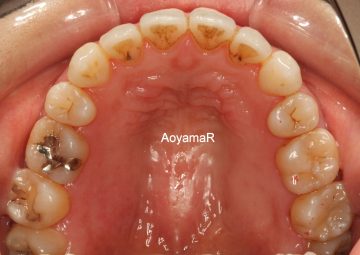

そう生(歯並びのガタガタ、乱杭歯、八重歯)の矯正症例

CASE 40

(25歳 女性 )

セクショナルアーチの治療

治療前